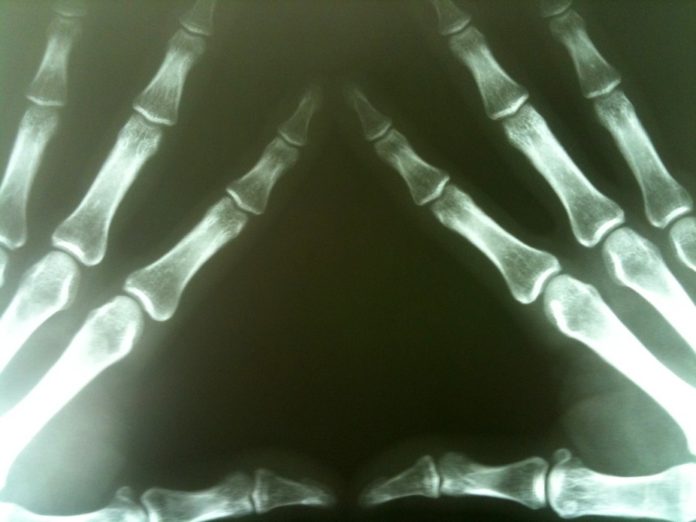

As more researchers investigate these cells and their network, the picture has become more elaborate. Osteocytes are clearly numerous and densely interconnected (see the image below), but putting an actual number on them had never been done. But it’s worth doing.